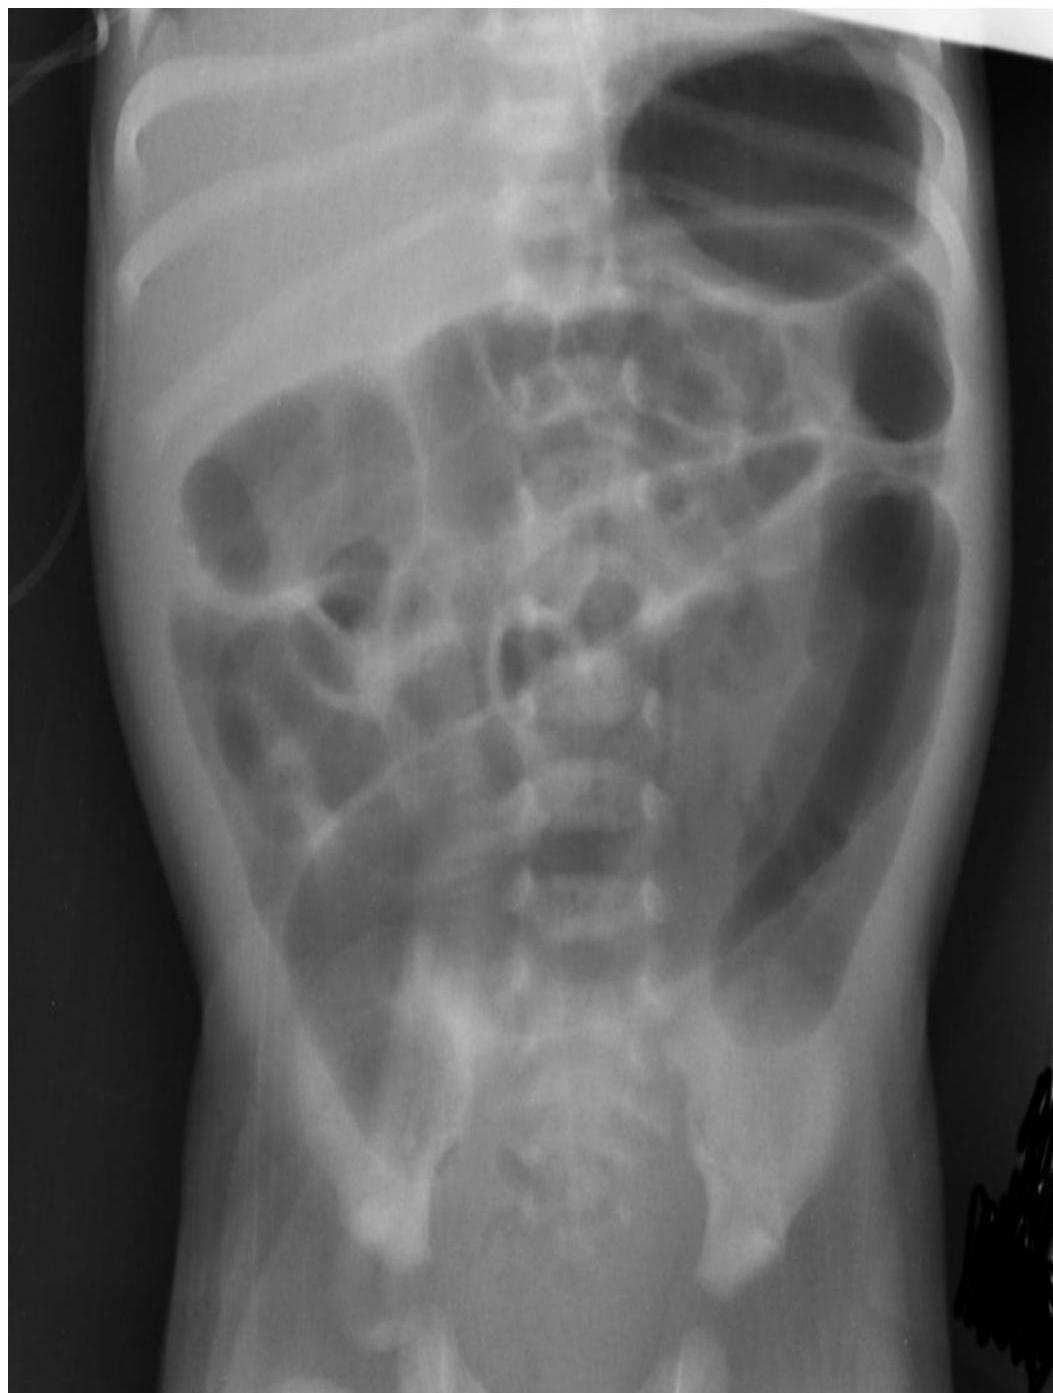

- Erect abdomen X-ray.

- Barium enema: Shows a transitional zone where a market change in caliber occurs, with the dilated normal colon above and the narrowed aganglionic below (should not be done in patient suspected of having enterocolitis → perforation).